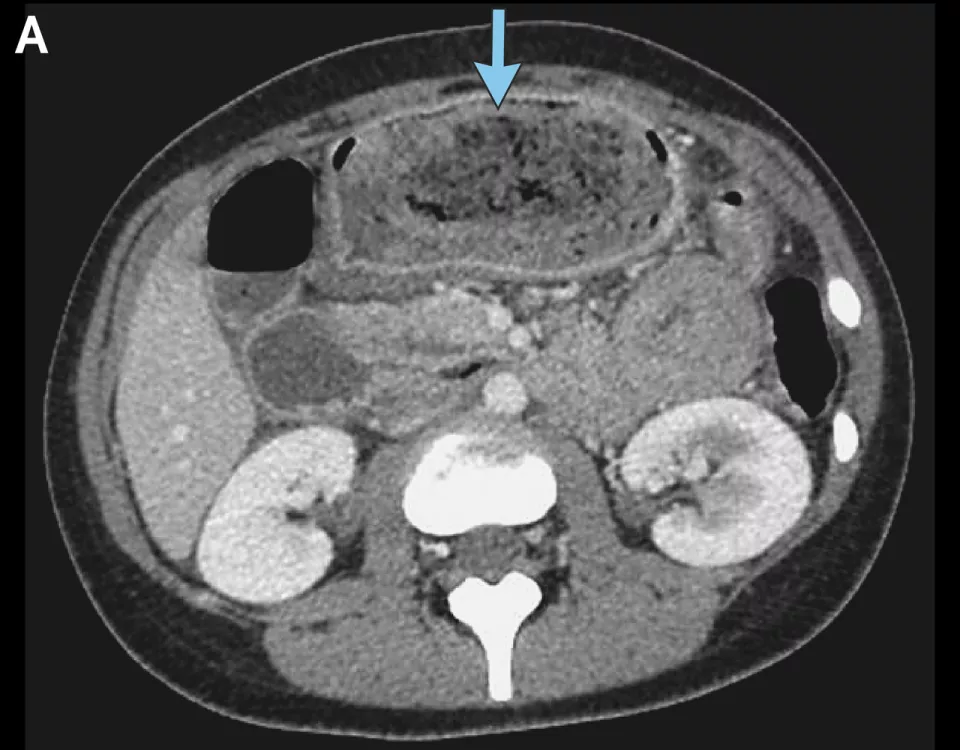

左滑查看更多图片:胃石示意图、手术中看到的毛发性胃石、CT检查中的胃石 | 参考文献[1]

胃石消失了 | 参考文献[1]